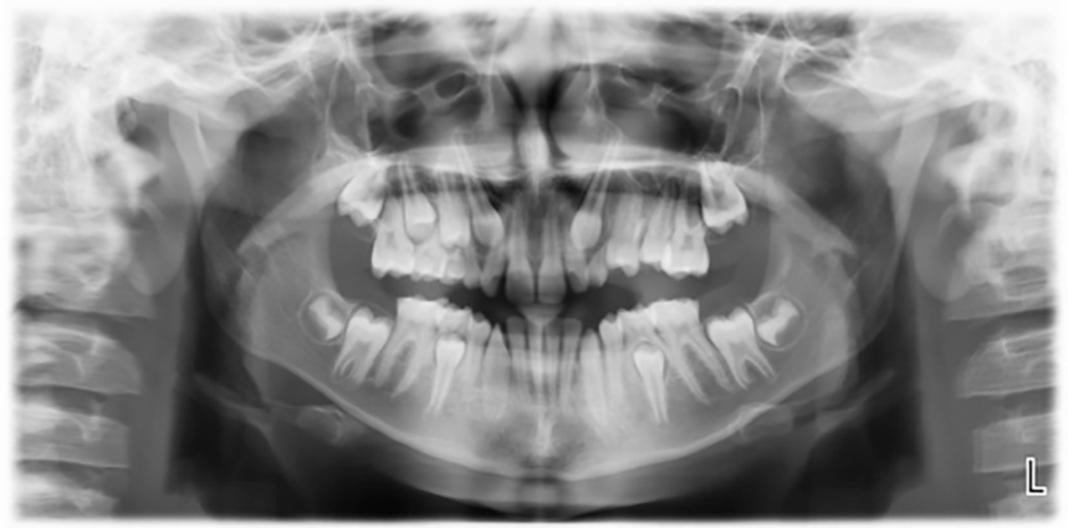

Tra le neoplasie odontogene pediatriche, il mixoma odontogeno (OM) rappresenta un’entità rara e benigna, con un’incidenza compresa tra l’8,5% e l’11,6% e un tasso di recidiva del 25% (1). Si caratterizza per una crescita lenta ma un comportamento localmente aggressivo, tanto da poter simulare, dal punto di vista clinico e radiologico, lesioni di natura maligna (2). La diagnosi definitiva richiede conferma istopatologica. In questo articolo viene presentato un caso clinico di mixoma odontogeno mascellare in età pediatrica, illustrando le fasi diagnostiche, l’approccio terapeutico adottato e il protocollo di follow-up attuato.

Among pediatric odontogenic neoplasms, odontogenic myxoma (OM) represents a rare and benign entity, with an incidence ranging from 8.5% to 11.6% and a recurrence rate of 25%1. It is characterized by slow growth but locally aggressive behavior, to the extent that it can simulate, from a clinical and radiological point of view, lesions of a malignant nature2. The definitive diagnosis requires histopathological confirmation. This article presents a clinical case of maxillary odontogenic myxoma in pediatric age, illustrating the diagnostic phases, the therapeutic approach adopted and the follow-up protocol implemented.